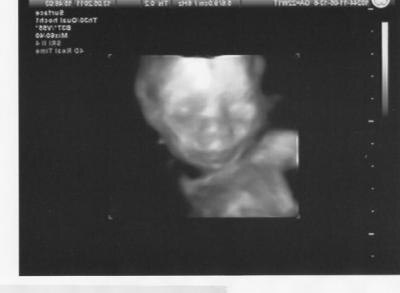

....und es ist alles super gut entwickelt und schaut gut und gesund aus. Es bleibt auch bei einem Mädchen. Dachte schon, er ändert sich doch noch mal... Das wäre doof gewesen...wir haben jetzt schon so viele Sachen in rosa gekauft. Allerdings meinte der Arzt, das sie für die 23 SSW schon recht gross ist. Sie ist 28 cm lang und rund 500 gr schwer. Ich muss jetzt einen Zuckertest machen. Sie hat sehr lange Beine meint der Arzt und meinte dann noch, das wenn etwas mit dem Zucker nicht passen würde, das Baby auch einen dicken Bauch haben müsste. Den hat unsere Kleine aber nicht, der ist durchschnittlich. Nur die Beine sind eben schon lang. Aber der Papa ist ja auch nicht gerade klein. Ansonsten war der Arzt sehr zufrieden. Aber ich mach mir dennoch etwas Sorgen wegen diesem Zuckertest und der Größe von unserer Süssen. Nicht das da doch etwas nicht stimmt. Hat da jemand Erfahrungen mit??? LG Sugar PS: Wir haben auch ein paar tolle 3D Bilder bekommen....so süsssssss

Bild zu Heute war FD.... - Forum für September - Mamis